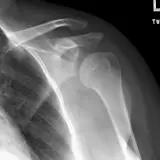

PACS์—์„œ ๊ธฐ๋Œ€ํ•  ์ˆ˜ ์žˆ๋Š” ๋ชจ๋“  ๋„๊ตฌ๋ฅผ ๊ฐ–์ถ˜ ์™„์ „ํ•œ ์ธํ„ฐ๋ž™ํ‹ฐ๋ธŒ ์ฆ๋ก€ — ์Šคํฌ๋กค, ์œˆ๋„์šฐ ์กฐ์ ˆ, ํ™•๋Œ€/์ถ•์†Œ, ํŒจ๋‹, ๊ณ„์ธก, ROI, ์ „์ฒด ํ™”๋ฉด ๋ชจ๋“œ๊นŒ์ง€ ์ง€์›ํ•ฉ๋‹ˆ๋‹ค.

์‹ค์ œ PACS ์›Œํฌ์Šคํ…Œ์ด์…˜์ฒ˜๋Ÿผ ์Šคํฌ๋กค, ํŒจ๋‹, ์œˆ๋„์šฐ ์กฐ์ ˆ, ํ™•๋Œ€/์ถ•์†Œ๊ฐ€ ๊ฐ€๋Šฅํ•ฉ๋‹ˆ๋‹ค